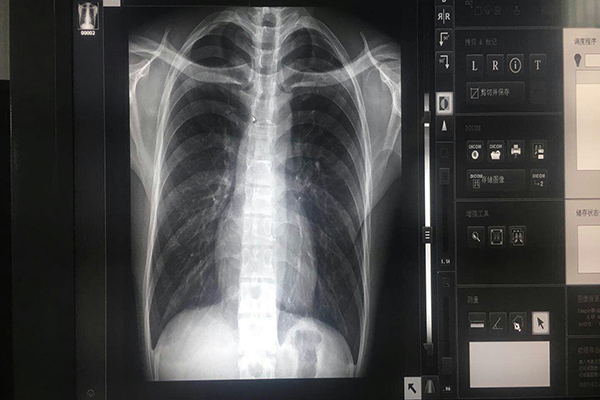

選配能進(jìn)行DICOM校正的顯示器,有專用校正軟件;顯示器背面有光學(xué)傳感器接口,可以接入光學(xué)傳感器進(jìn)行校正,否則無法進(jìn)行校正。選配有亮度恒定裝置的放射監(jiān)視器,以保證顯示器的亮度不隨時(shí)間變化,它可以保證系統(tǒng)顯示器的一致性和整體性。